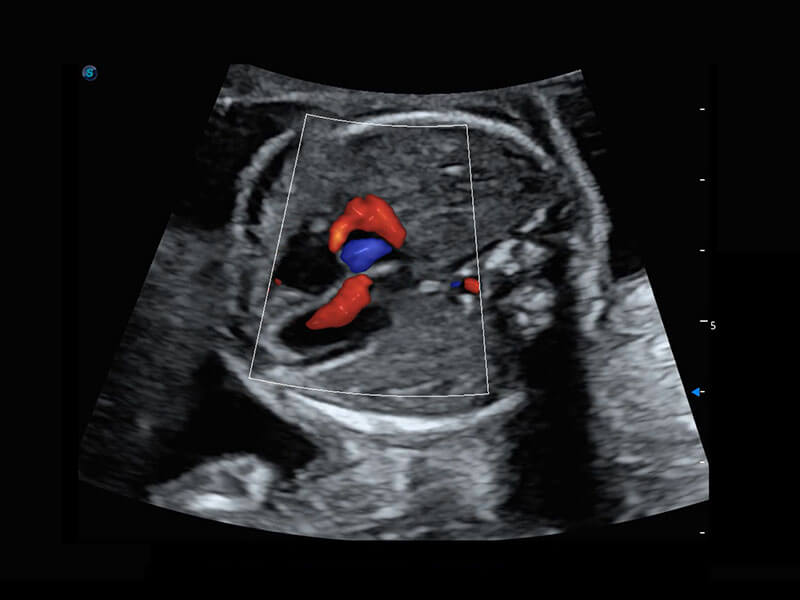

P60搭载一系列胎儿心脏成像技术,实现精细的胎儿心脏评估。

四腔切面

四腔心血流

右室双出口

胎心容积成像